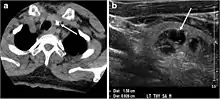

- Fig. 7. A 51-year-old female patient post total thyroidectomy for PTC with elevated thyroglobulin measurement. an Axial non-enhanced CT scan of the neck at the level of the thyroid bed demonstrates a well-defined, rounded, homogenously dense soft tissue situated between the trachea and left internal jugular vein (white arrow). b Transverse ultrasound image of the neck demonstrates a well-defined, homogeneous, hypoechoic soft tissue nodule measuring 6 mm (white arrow) with no detected micro-calcifications. Biopsy showed a predominantly residual normal thyroid tissue with micro-foci of PTC.[1]

- Fig. 8. A 48-year-old male patient post total thyroidectomy with PTC recurrence. a Transverse greyscale ultrasound of the neck demonstrates a left thyroid bed heterogeneous, predominantly hypoechoic irregular lesion with calcifications (white arrow). b A spot image of iodine 123 total body scan of the neck demonstrate a focus of abnormal radiotracer uptake at the left thyroid bed (Black arrows) between the annotated markers. c Enhanced axial CT scan of the neck demonstrates an enhancing large left thyroid bed mass (white arrow) with no calcifications. The lesion exerts a mass effect on the oesophagus (black arrow) and is inseparable from the trachea.[1]